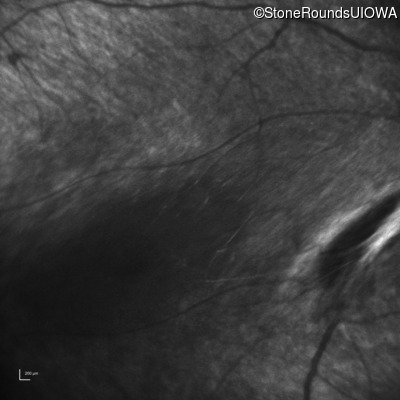

Infrared Fundus Photograph - Right - No Light Perception

Exemplar